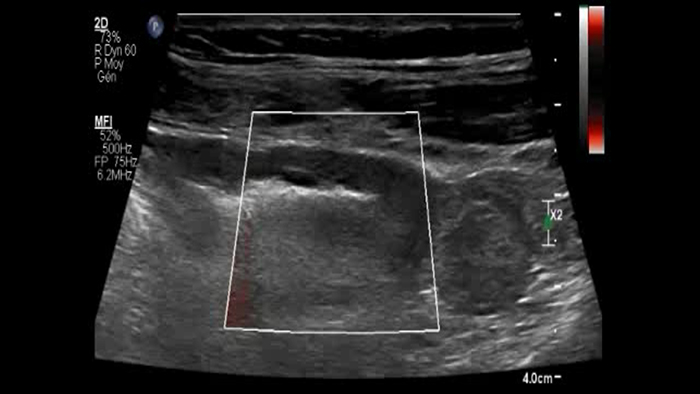

Ces images précises des lésions des couches pariétales forment la base de l’interprétation des changements induits par l’inflammation des parois intestinales et par conséquent de la différenciation entre la maladie de Crohn et la rectocolite hémorragique. L’exploration avec la technologie MFI (MicroFlow Imaging) constitue la deuxième étape. Il s’agit de reconnaître l’aspect de l’hypervascularisation induite par des épisodes inflammatoires actifs. La paroi intestinale normale semble comporter peu de microvaisseaux détectables, uniquement à l’interface de la muqueuse et de la sous-muqueuse, et dans le tissu adipeux mésentérique adjacent. Inversement, la paroi inflammatoire présente de nombreux microvaisseaux. La distinction entre les images d’artefacts de mouvement et les microvaisseaux circulants est alors un point essentiel nécessitant un ajustement parfait des paramètres de détection des micro-flux (voir les boucles, diapositive 8). La comparaison des 4 images suivantes de la maladie de Crohn met en évidence des différences claires qui devraient être interprétées comme étant représentatives des différents états inflammatoires. L’image 1 ne comporte aucun vaisseau visible, ce qui correspond probablement à une absence d’activité. L’image 2 présente quelques vaisseaux ; nous pouvons en conclure que cela correspond à une activité modérée. L’image 3 comporte un plus grand nombre de vaisseaux, signe probable d’une activité intense. L’image 4 présente encore plus de vaisseaux de type pulsatile, ce qui évoque probablement une activité très intense.

No vessel no activity ?